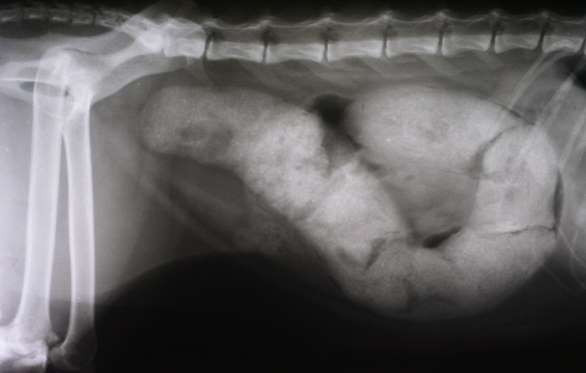

6 dấu hiệu cảnh báo ung thư dạ dày ảnh 1

Dấu hiệu điển hình của đau liên quan đến ung thư dạ dày là dai dẳng và "dấm dứt”, chứ không phải lúc có lúc không. Ngoài ra, đau do ung thư dạ dày “kinh điển” là đau ở vùng giữa bụng.